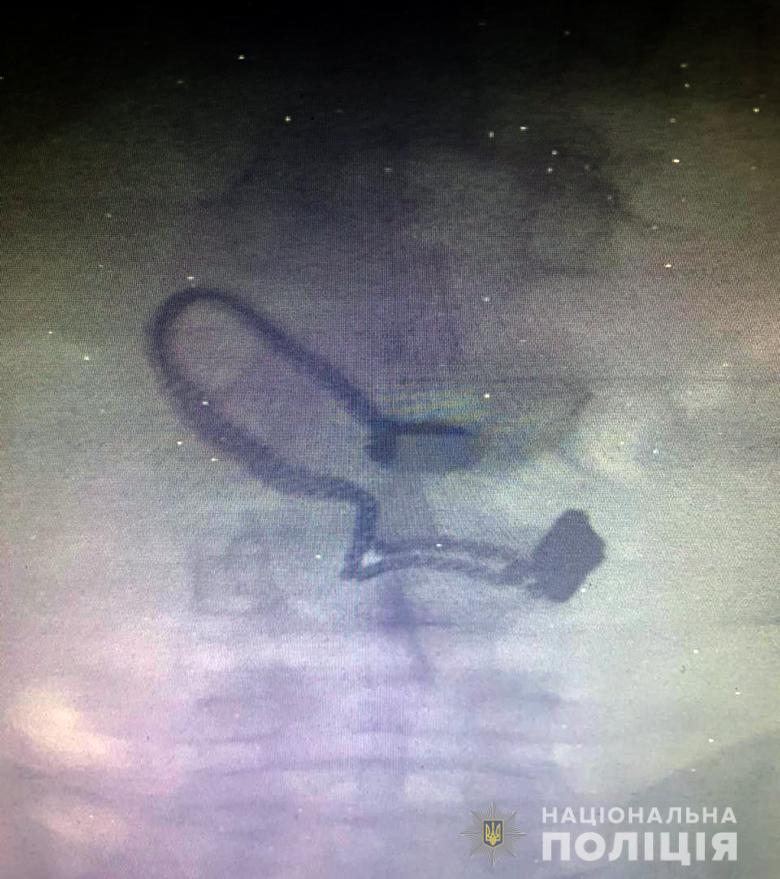

Украшение обнаружили на рентген снимке. Столичные жители задержали мужчину, который отобрал у 73-летней прохожей кошелек, сорвал с ее шеи цепочку и проглотил ее.

Во время медосмотра на рентген снимке задержанного врачи обнаружили украшение. По данному факту начато уголовное производство по части второй статьи 186 (грабеж) Уголовного кодекса Украины. Фигуранту объявили о подозрении. За содеянное ему грозит до шести лет лишения свободы.